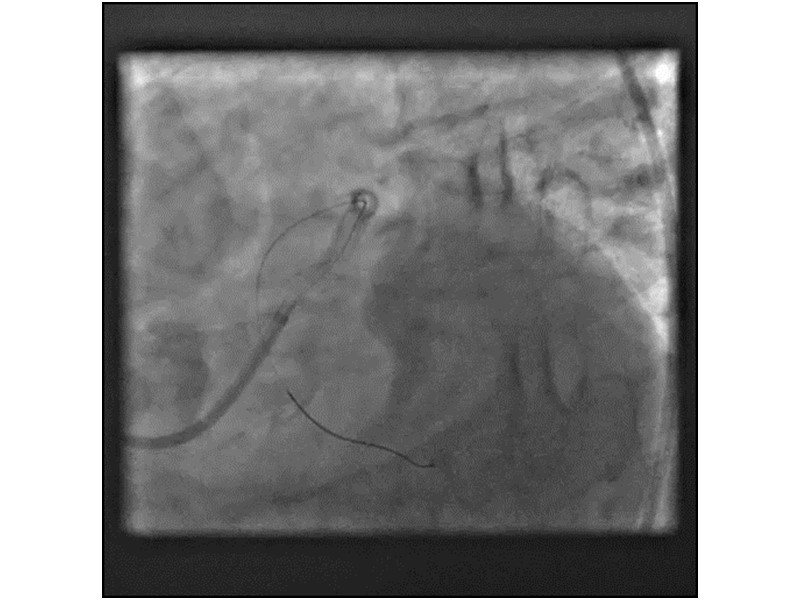

Distal left main stenosis: how to treat optimally with dedicated bifurcation stent BiOSS Lim C. Case-based session

Consult this session to learn more about the multiple technological options with dedicated bifurcation stent for complex left main bifurcation lesions, and the applicability of this stent for the different clinical presentations.